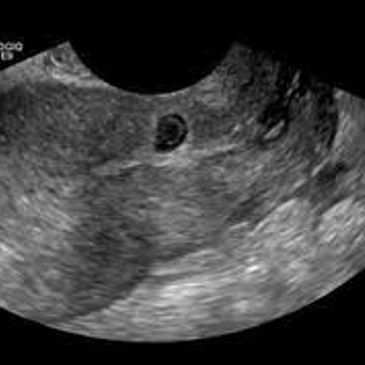

This is a rare pregnancy that has implanted at the site of a previous Caesarean section scar. This is an extremely high-risk pregnancy that in very select cases are allowed to continue and sometimes result in a live birth. In most cases, treatment with intra-sac and systemic methotrexate is recommended. However, due to the prolonged admission associated with methotrexate treatment, surgical management by an expert gynaecologist should be considered.

In many cases, treatment with intra-sac and systemic methotrexate is recommended. However, due to the prolonged admission associated with methotrexate treatment, surgical management by an expert gynaecologist should be considered. Particularly if the Caesarean scar pregnancy is classified as type 1, which means the gestational sac is developing towards the endometrial cavity, surgical management can sometimes be a straightforward suction curettage. With a type 2 Caesarean scar pregnancy on the other hand (see picture above), laparoscopic removal of the Caesarean scar pregnancy by an experienced set of hands is required. One advantage of the laparoscopic approach is that the Caesarean scar defect can be excised and repairs at the same time.